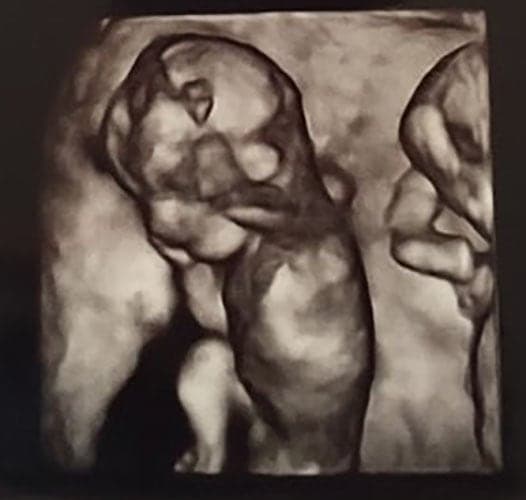

Ultraschallbilder aus dem 3. Trimester (29. bis 40. SSW)

Im dritten Trimester der Schwangerschaft ist das Baby so groß, dass es nicht mehr komplett auf ein Ultraschallbild passt. Nun kann man wunderbare 3D-Ultraschalle des Gesichts machen. In diesem Semester nehmen die Babys nochmal rasant zu und wer Glück hat, kann auf seinem Ultraschall schon erste Gesichtszüge erkennen.